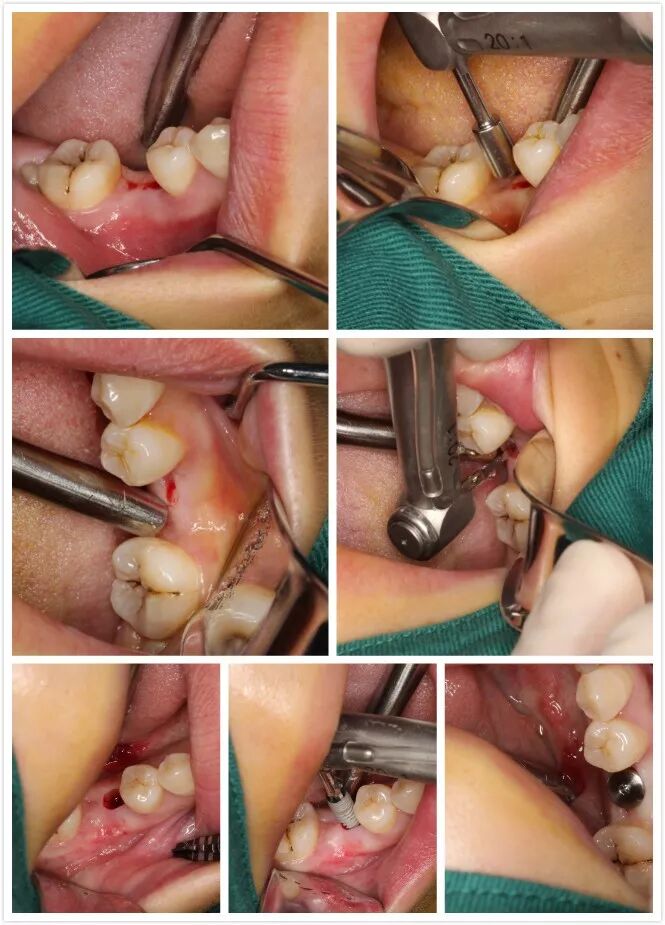

1 讲师简介 梁光强老师 (毕业于首都医科大学) 2 课程安排 第一天 1、口腔种植的基本概念 2、口腔门诊开展简单种植应该了解的基础知识 3、拓展种植牙业务医患交流技巧 4、民营口腔如何开展种植牙项目 5、开展种植所需要的设备,耗材以及所需要的准备工作 6、种植体的表面处理 7、如何读懂X光片 8、种植术前的评估--步骤与方法 9、缝合原则 10、{实习操作}缝合练习,种植X片的现场评估 第二天 1、种植牙手术术前准备 2、种植牙术中,术后的注意事项 3、种植手术植入流程 4、修复方式选择 5、印模技术 6、种植二期上部结构修复 7、门诊观看种植牙手术 8、{实习操作}种植植入模型实际操作 第三天 1、种植牙修复的并发症及处理方式 2、简单上颌窦提升技术 3、即刻种植 4、{实习操作}种植修复二期取模实际操作 3 病例展示 病例一 4 招生信息 主题:《走进民营-快速开展种植牙》 时间:2022年3月8日—3月10日 地点:宗言公司 主讲:梁光强老师 费用:老学员3600元/人(不含税)新学员3800元/人(不含税) 主办方:宗言牙材 注:公司站学习免费提供食宿 专车接送 长按二维码关注我们 更多精彩内容尽在 www.zongyan.com